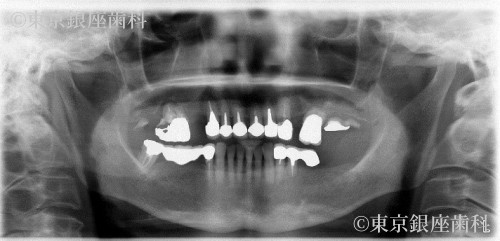

複数の奥歯を長期間失い、前歯に過度な咀嚼力の負担がかかってしまったため、全顎的にインプラントを支台とした口腔機能回復が必要となった症例

初診時のお口の状態は、複数の奥歯が抜けていて、残っている奥歯も歯周病や、虫歯・根尖病巣により予後が不良(長期的に歯の保存が望めない)な状態でありました。

また、奥歯で物を噛めないため前歯で咀嚼を長期にわたり行うことで、前歯への力の負担が強くなり歯の根がヒビが入ったり、折れてしまっている状態でした。

上顎に関しては上記の理由により最小本数のインプラントを支台とした全顎的な人口歯によって口腔機能の回復を予定しました。

また右側の奥歯にインプラントを埋入するのに必要な骨の高さが不足していたため、上顎洞と呼ばれる空洞に骨をたす治療(サイナスリフト)も並行して行い、インプラントを安定させるための必要な骨の高さを得る予定を立てました。

下顎は奥歯にかぶせ物の治療をすることで奥歯の咀嚼機能を回復する予定を立てました。